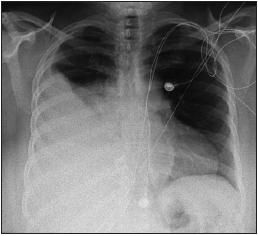

Physical examination revealed an obese woman with markedly decreased air entry over the mid and lower right hemithorax. A chest radiograph (Figure 1) and a CT scan showed a large right-sided pleural effusion with atelectasis of the right lower lobe.

Figure 1 – A large right sided pleural effusion with atelectasis of the right lower lobe can be seen in this chest radiograph. The patient had presented with worsening shortness of breath and a 50-lb weight loss.